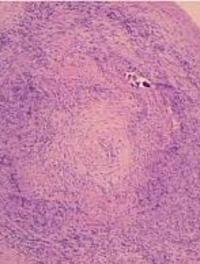

Le traitement purement symptomatique de l’artérite à cellules géantes de Horton repose principalement sur la corticothérapie dont l’efficacité [...]